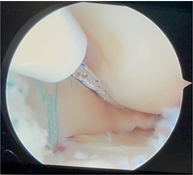

Fixation of the anterior soft tissue plug

Anterior root fixation is performed after insertion of the posterior meniscus root bone plug. This sequence allows you to have a more precise idea about the correct location. The imprint of the anterior horn of the medial meniscus is located in front of the tibial insertion of the ACL, behind the intermeniscal ligament.

The insertion of the lateral anterior meniscal horn can be found in front of the lateral eminence.

The insertion of the anterior horn of the meniscus is recreated with the knotless suture anchoring device, we prefer to use PEEK Swivelock type 4.75 mm (Arthrex), the anchor insertion angle is approximately 60-70° in the sagittal plane (up to the tibial plateau).

The anterior horn is fixed with the use of a 4.75 mm Swivelock anchor

Adequate stability and tension of the entire periphery is confirmed before fixing the posterior bone plug.